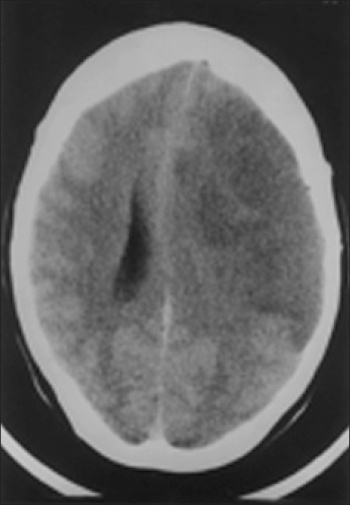

Cerebral oedema post-stroke occurs due to the breakdown of neuronal cell membranes, cytotoxic oedema, and by disruption of the blood-brain barrier, vasogenic oedema. It may be seen in large middle cerebral artery infarcts, the so-called malignant cerebral infarction, or in haemorrhagic strokes (see Figure 1). Cerebral oedema may result in temporal lobe herniation, brainstem compression, hydrocephalus, and reduced cerebral blood flow. Glycerol,10 mannitol,11 and steroids12 have not been found to improve prognosis in stroke-related cerebral oedema.

Figure 1: Left MCA infarction with cerebral oedema and midline shift

Figure 1: Left MCA infarction with cerebral oedema and midline shift(click to enlarge)